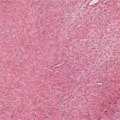

病理写真

摘出した腫瘤の病理組織検査の結果、“軟部組織肉腫(中間悪性度)”と診断、摘出状態も良好と確認された。軟部組織肉腫は局所浸潤性が強い腫瘍である。また、本症例の腫瘤は巨大で、腋窩部という摘出が難しい場所に形成されていた。断脚術を併用したことで完全摘出が可能となったと考えられる。術後の経過も良好である。